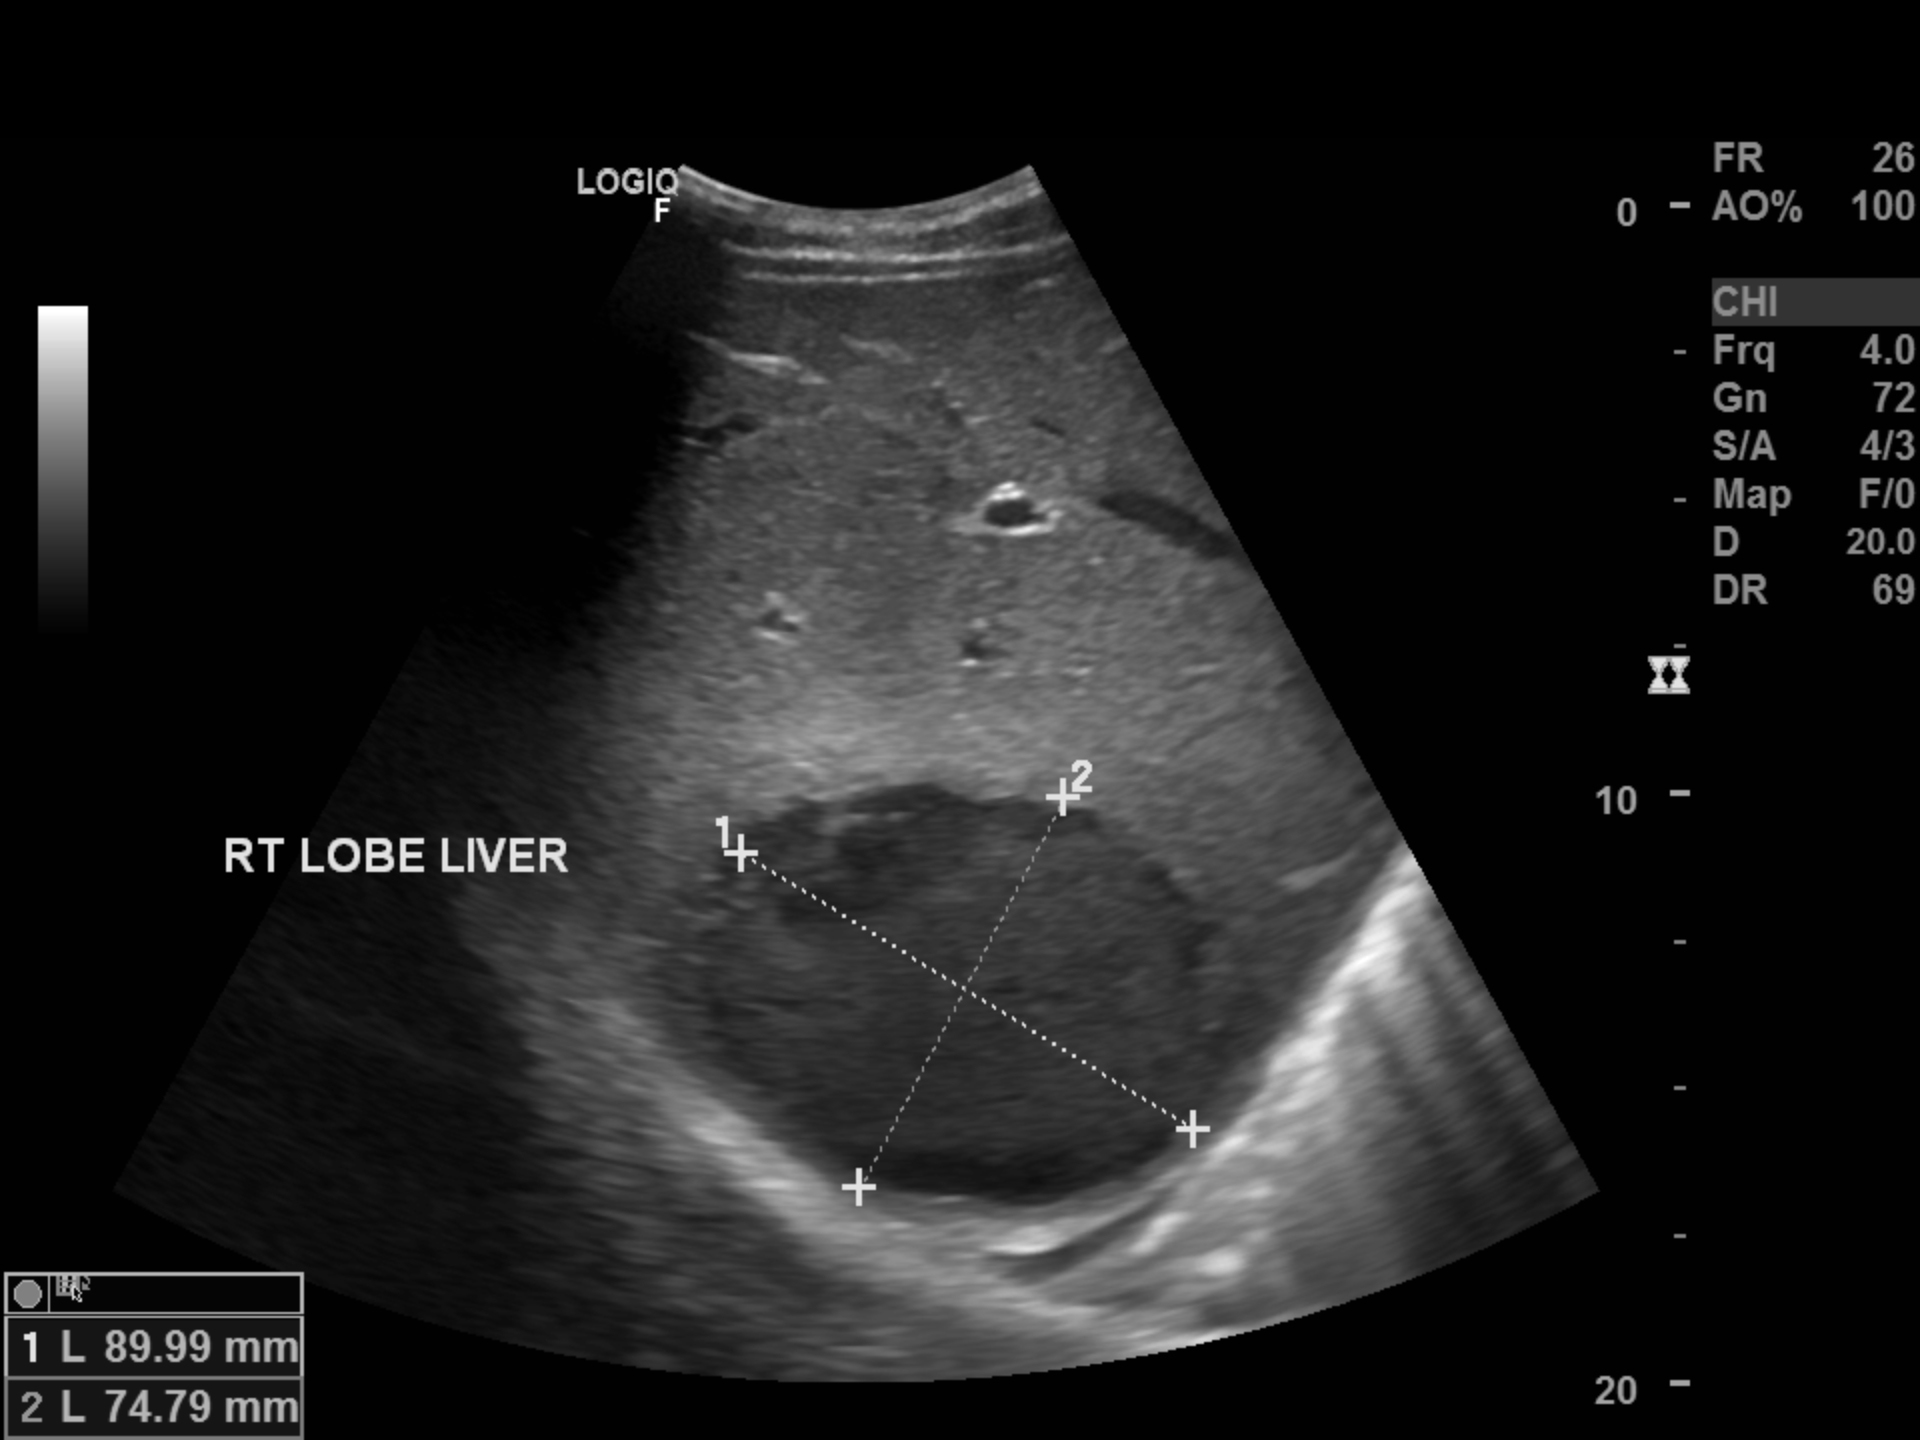

Абсцесс печени — заболевание, возникающее в результате гнойного воспаления тканей печени, их отмирания и образования полости, заполненной гноем . . . . фото, признаки и лечение . . .

К75 .0 . Абсцесс печени . А06 .4 . Амёбный абсцесс печени . Патология По морфологическим характеристикам выделяют солитарные, множественные и милиарные абсцессы печени .

Абсцесс (от лат . abscessus — «гнойник», «нарыв») печени представляет собой единичное или множественное очаговое воспаление с образованием в ткани печени одного или нескольких опухолевидных . . .